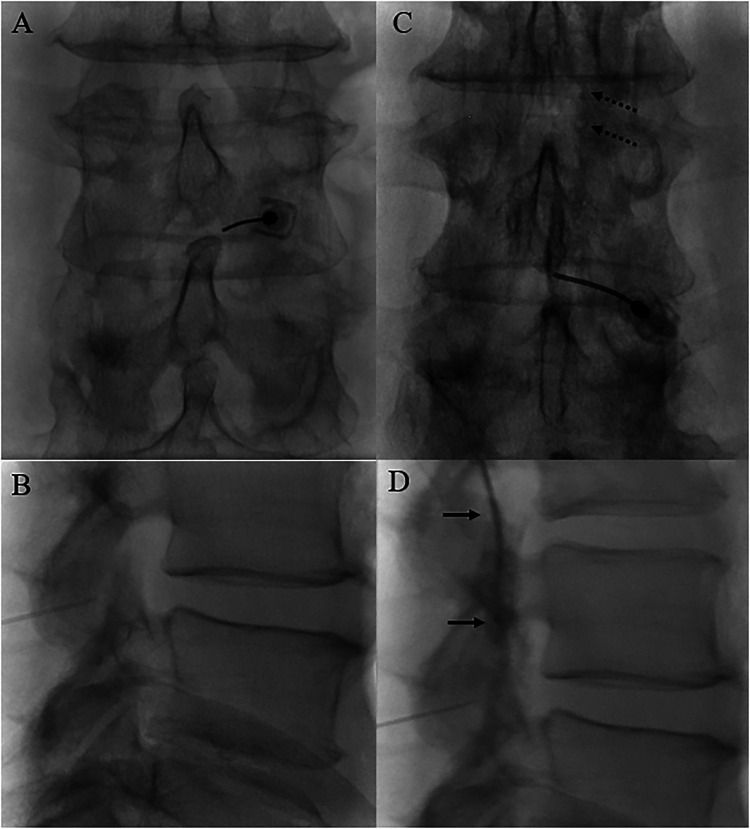

2. Fluoroscopic guidance: Same setup as TFESI — AP view to identify level, then oblique to visualize the foramen

3. Needle placement: Same periforaminal target as TFESI, using a 22-25 gauge spinal needle

4. Contrast injection first: Inject 0.1-0.3 mL of contrast to confirm position and observe the spread pattern — critical to verify limited, localized spread

• A retroneural approach with more lateral needle tip placement improves selectivity by directing injectate to the spinal nerve

• Diagnostic SNBs require unique targeting more laterally at the foramen with severely limited injection volumes to prevent distribution into the central epidural space medially or the plexus laterally.